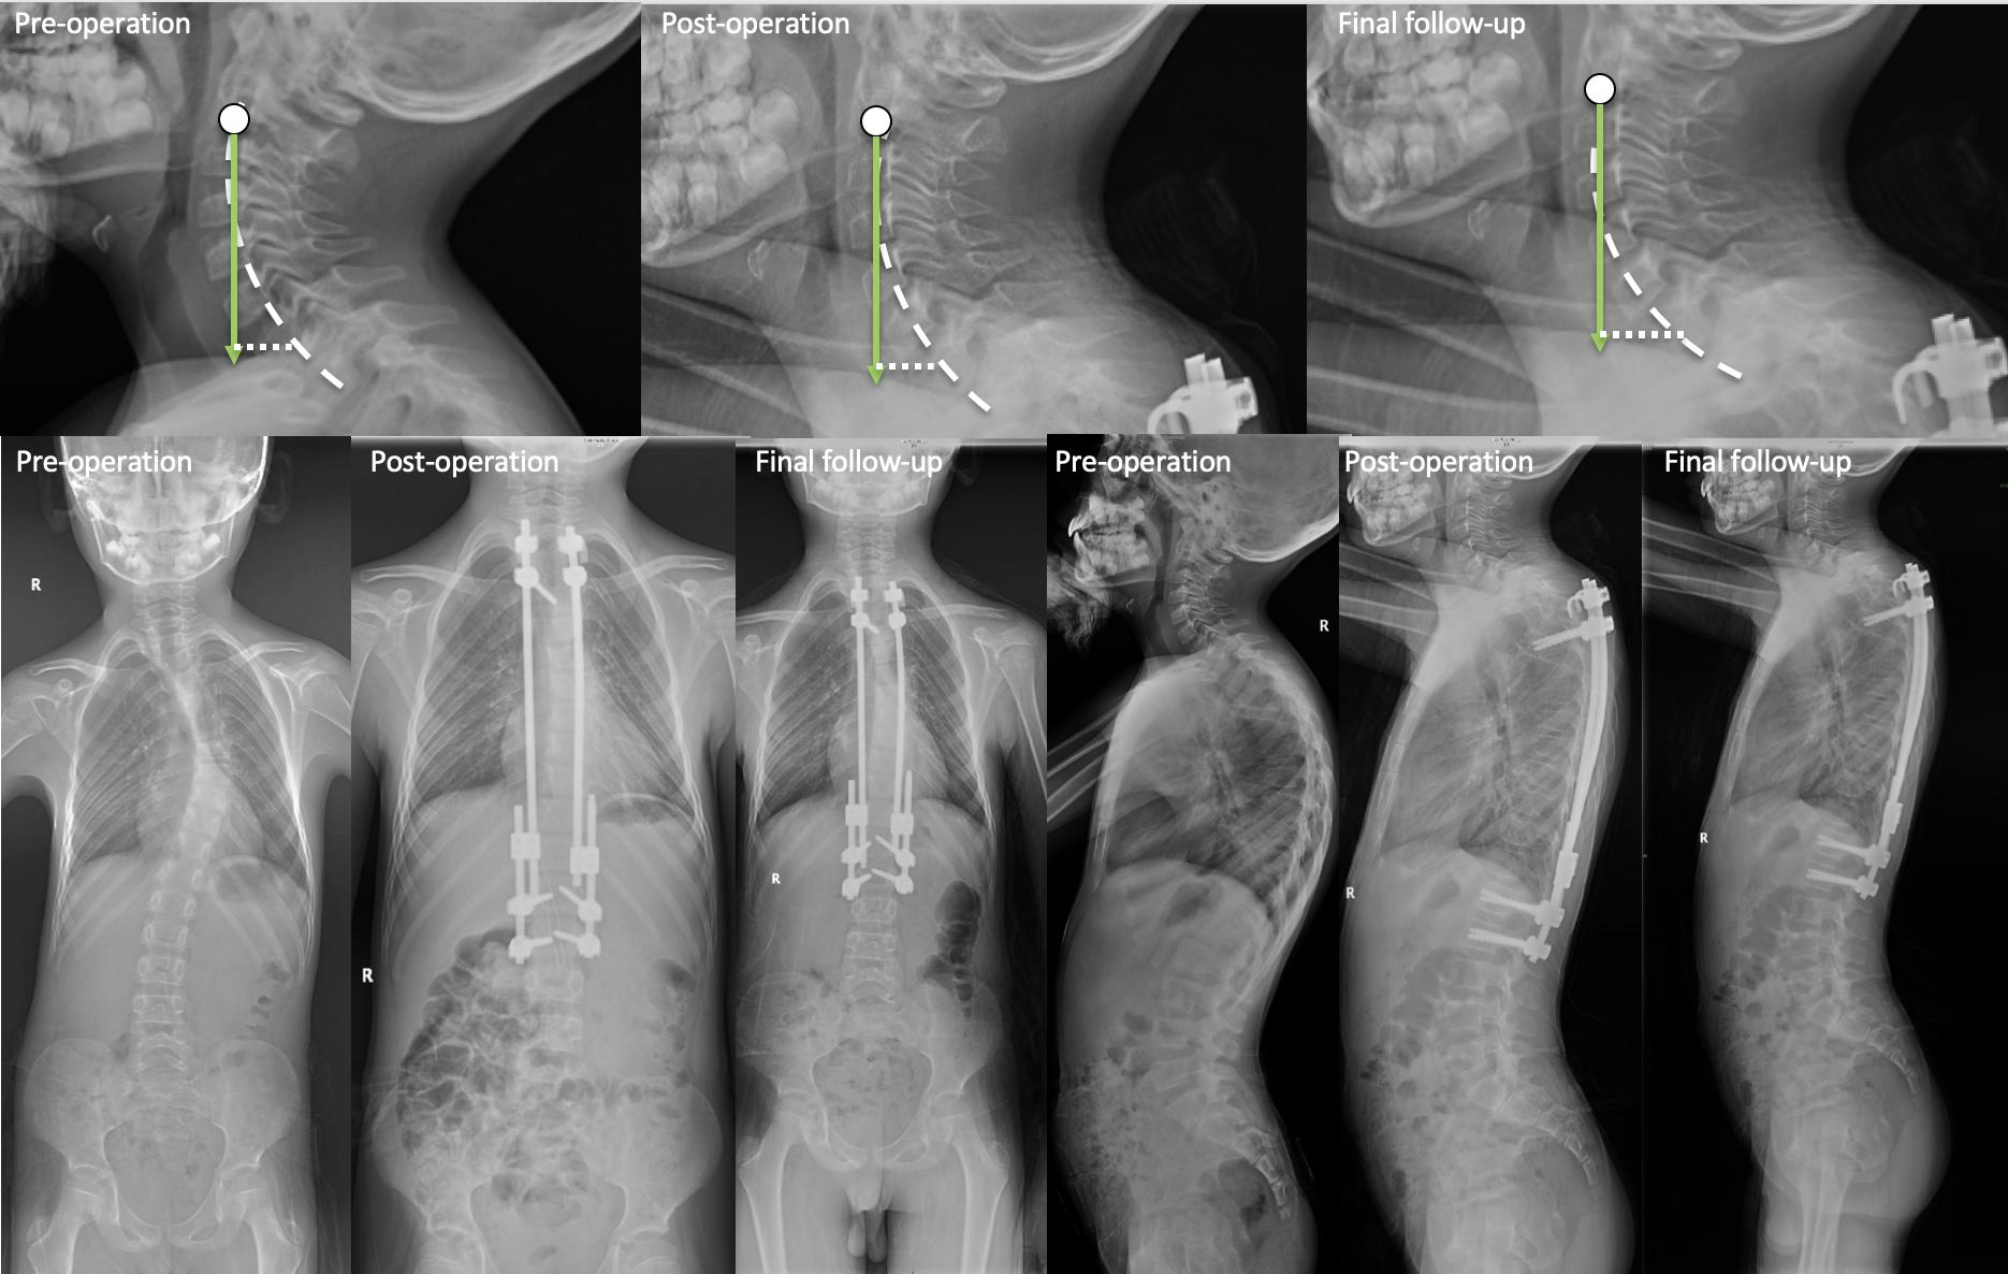

Fig. 6

During growing rod treatment, the cervical sagittal balance changes in the patient without PJK. (It is a 10-year-old male patient diagnosed with idiopathic EOS. After the 2nd distraction, scoliosis and hyperkyphosis are corrected well. In the final follow-up, he does not have PJK above the growing rod. Sagittal cervical alignment change: C2-C7 CL increases from 57.9° to 62.9°, T1 slope increases from 48.1° to 57.4°, and C2-C7 SVA increases from 22.5 mm to 24.5 mm.)